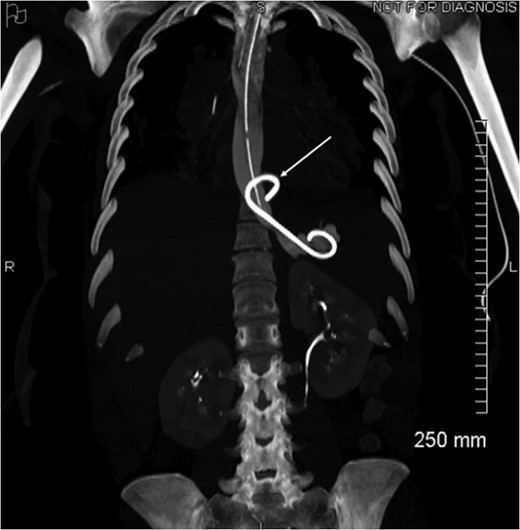

Coronal view of opacification on CT showing the externalization of the drain in the pericardium (arrow).